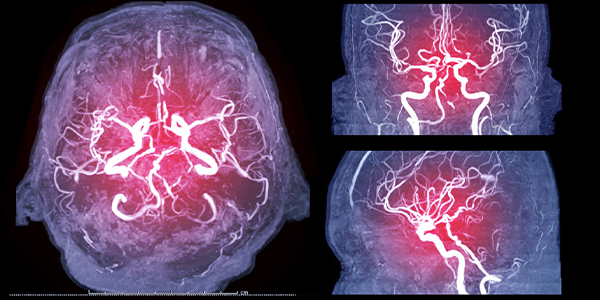

Beyin anjiyografisi, beyin damarlarının detaylı bir görüntüsünü sunarak şu avantajları sağlar:

• İnme ve anevrizma gibi ciddi damar hastalıklarını erken teşhis etme imkânı

• Cerrahi veya invaziv tedavi planlamasında yardımcı olma

• Diğer görüntüleme yöntemleriyle belirlenemeyen damar anomalilerinin tespiti

Beyin Anjiyografi Sonuçları Nasıl Değerlendirilir?

İşlem sonrası elde edilen görüntüler uzmanımız tarafından değerlendirilir. Beyin damarlarında tıkanıklık, anevrizma veya daralma varsa, uygun tedavi seçenekleri hastaya sunulur:

• Endovasküler tedavi (stent veya balon yerleştirme)

• Anevrizma onarımı

• Kan sulandırıcı ilaç tedavisi